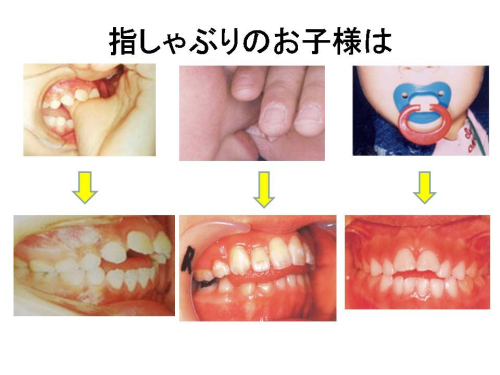

指しゃぶりは歯並びを悪くする原因の一つです。私は3歳ぐらいまでは指しゃぶりは異常とはいえませんので、無理にやめさせる必要はありませんが、3歳を過ぎたら、指しゃぶりは徐々にやめさせるように一般的には注意をさせていただいております。大きくなっても指しゃぶりを続けることによって、歯の並び方だけではなく、顎の成長にも大きく影響を与えます。指のしゃぶり方によっても違いますが、開咬(噛み合わせたとき、後ろの歯だけ噛み合わさり、前歯で噛むことができない、口がいつも開いた状態になっている)や下あごを押さえるように指をしゃぶる場合、下あごの成長が抑制されて骨格的な出っ歯になってしまう場合もあります。さらにこれが発端となり弄唇癖(ろうしんへき)(下唇を前歯で噛んだり、吸い込んだりする癖のことの総称)・舌突出癖(“舌の癖”がある子どもは,呑み込むときに上下の前歯の間に瞬間的に舌を押し出します。)を起こし、後に口呼吸の原因になることがあります。

開咬

指しゃぶりをする指の種類や場所にかかわらず、強く指しゃぶりをするお子様ほど、強く影響があらわれます。しかし、やめさせるための私たち歯科医師からの指導は、お子様の身体的・精神的成長発達やお子様を取り巻く家庭環境等を考慮して慎重に行う必要があります。

指しゃぶりをするからと言って必ず開咬や上顎前突になるとは限りません。開咬や上顎前突になってしまう指しゃぶりは、その頻度・強さ・時間等によって影響されるので、お子様の現状をしっかりと診断し、お子様の状況に合わせた指導をお母様に行うよう心がけています。

例えば、多少の悪影響がではじめても、早期に指しゃぶりの習癖が消失するかおしゃぶりを取ることができ、口腔周囲筋の発達に問題がなければ、自然治癒する可能性が高いです。

一般的に指しゃぶりを始めて、1年未満では大きな影響は認められませんがしかし、強い習癖が1年半以上続くと、1.6才健診でその弊害の兆候が見られ始め、3才の健診時にはすでに開咬や上顎前突になってしまっている場合が多くみられます。指しゃぶりは、いったん強くなってしまうと止めさすことは難しく、年齢が上がれば上がるほど、止めさせる難易度は増してしまうように思います。また、強く悪影響が出始めたからと言って、私たち歯科医師が不容易に強く指導することは、色々な事情を抱えたお母様に過剰なストレス等の精神的負担を増加させ、かえって健全な母子関係にヒビをいれる可能性もあり、私たち歯科医師も慎重な対応が必要とされます。